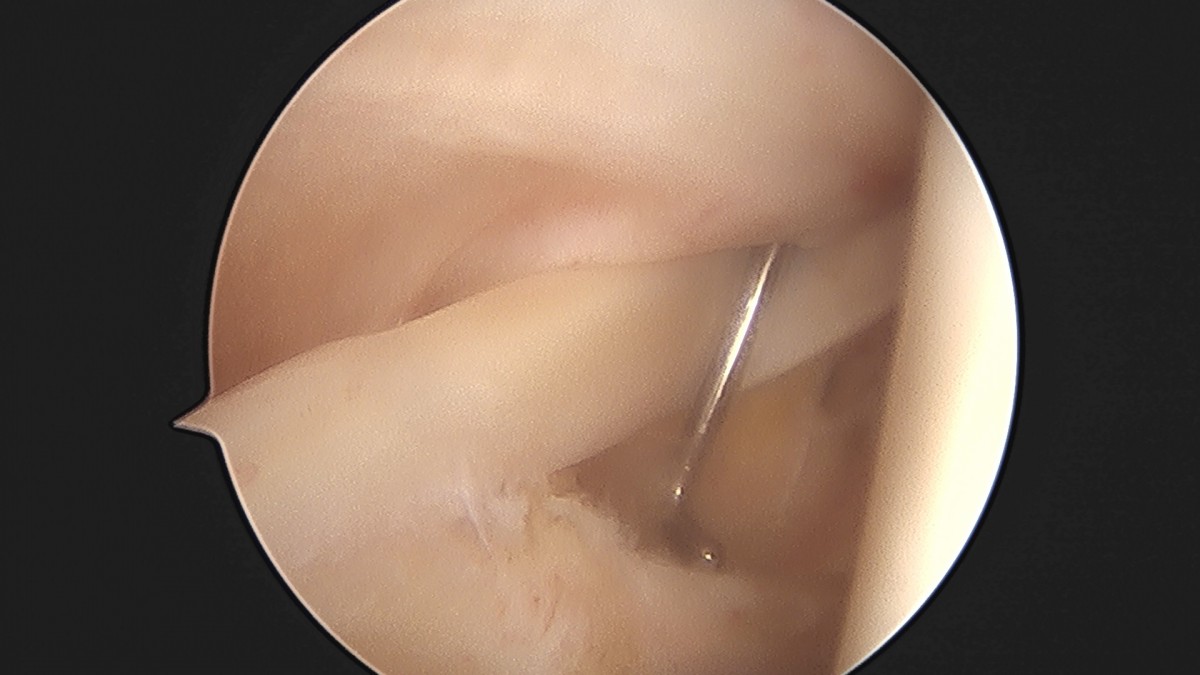

이재상원장님 어깨 석회 제거술 조광O 환자

작성자 최고관리자 댓글 0건 조회 799회 작성일 25-09-16 15:38